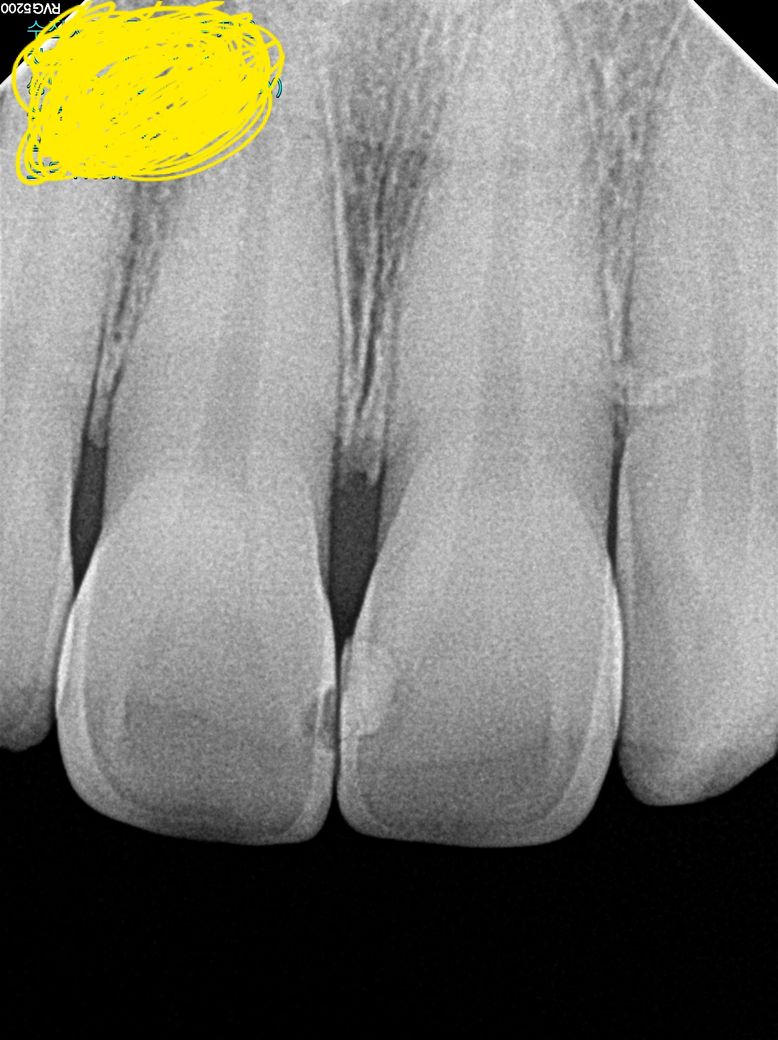

• 2번 째 사진

직접확인을 해봐야 알겟지만 엑스레이 상으로 까맣게 보이는 부분은 뭔가 떨어져 나갓거나 충치가 잇는상태입니다.

1. 큰 사진이 파노라마 방사선 사진이고, 작은 사진이 치근단 사진이며 치근단 방사선 사진상(노란색으로 표시하신 사진 기준) 왼쪽이 11번 치아, 오른쪽이 21번 치아 입니다. 만약 두 치아를 동일한 재료로 떼우신 거라면 11번은 기존 재료가 떨어져 나간 상태로 보입니다.

두번째 사진에서

왼쪽이 11번 입니다. 옆면 충치가 보입이다

오른족이 21번 입니다. 예전에 레진(?)으로 충치제거 후 떼운 치료를 받으신 것으로 판독됩니디.

도움이 되셨기를 바랍니다.